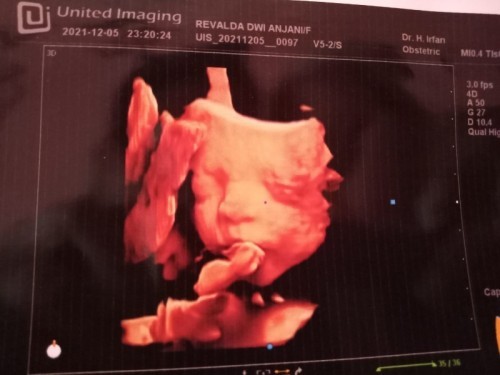

hasil usg anak pertama kehamilan 25-26 week

bun mau nanya dong disini ada bunda bunda yg Hamil 25-26 week udaa usg? sedikit cerita ya bun nah kemarin aku usg trus kata dokter JK nya laki laki berat badan janinnya 870 gram alhamdulillah letak kepalanya sudah dibawah ketuban normal letak plasenta nya juga bagus ga nutupin jalan lahir detak jantung janinnya 141/menit bun kata orng orng sih djj cowo lambat sedangkan kalo djj cewe cepet makanya bingung antara percaya atau engga soalnya dokter bilangnya jk cowo karna keliatan ada bijinya bantu sharing dong bun soalnya mau beli perlengkapan bayi masi ragu takutnya pas lahir beda gitu sama hasil usg:(( #seriusnanya #bantusharing